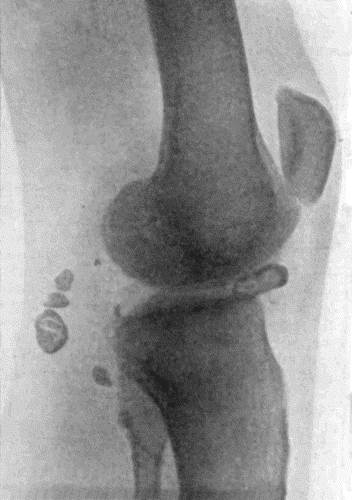

162.Bones of Knee in Charcot's Disease 533

163.Charcot's Disease of Left Knee 534